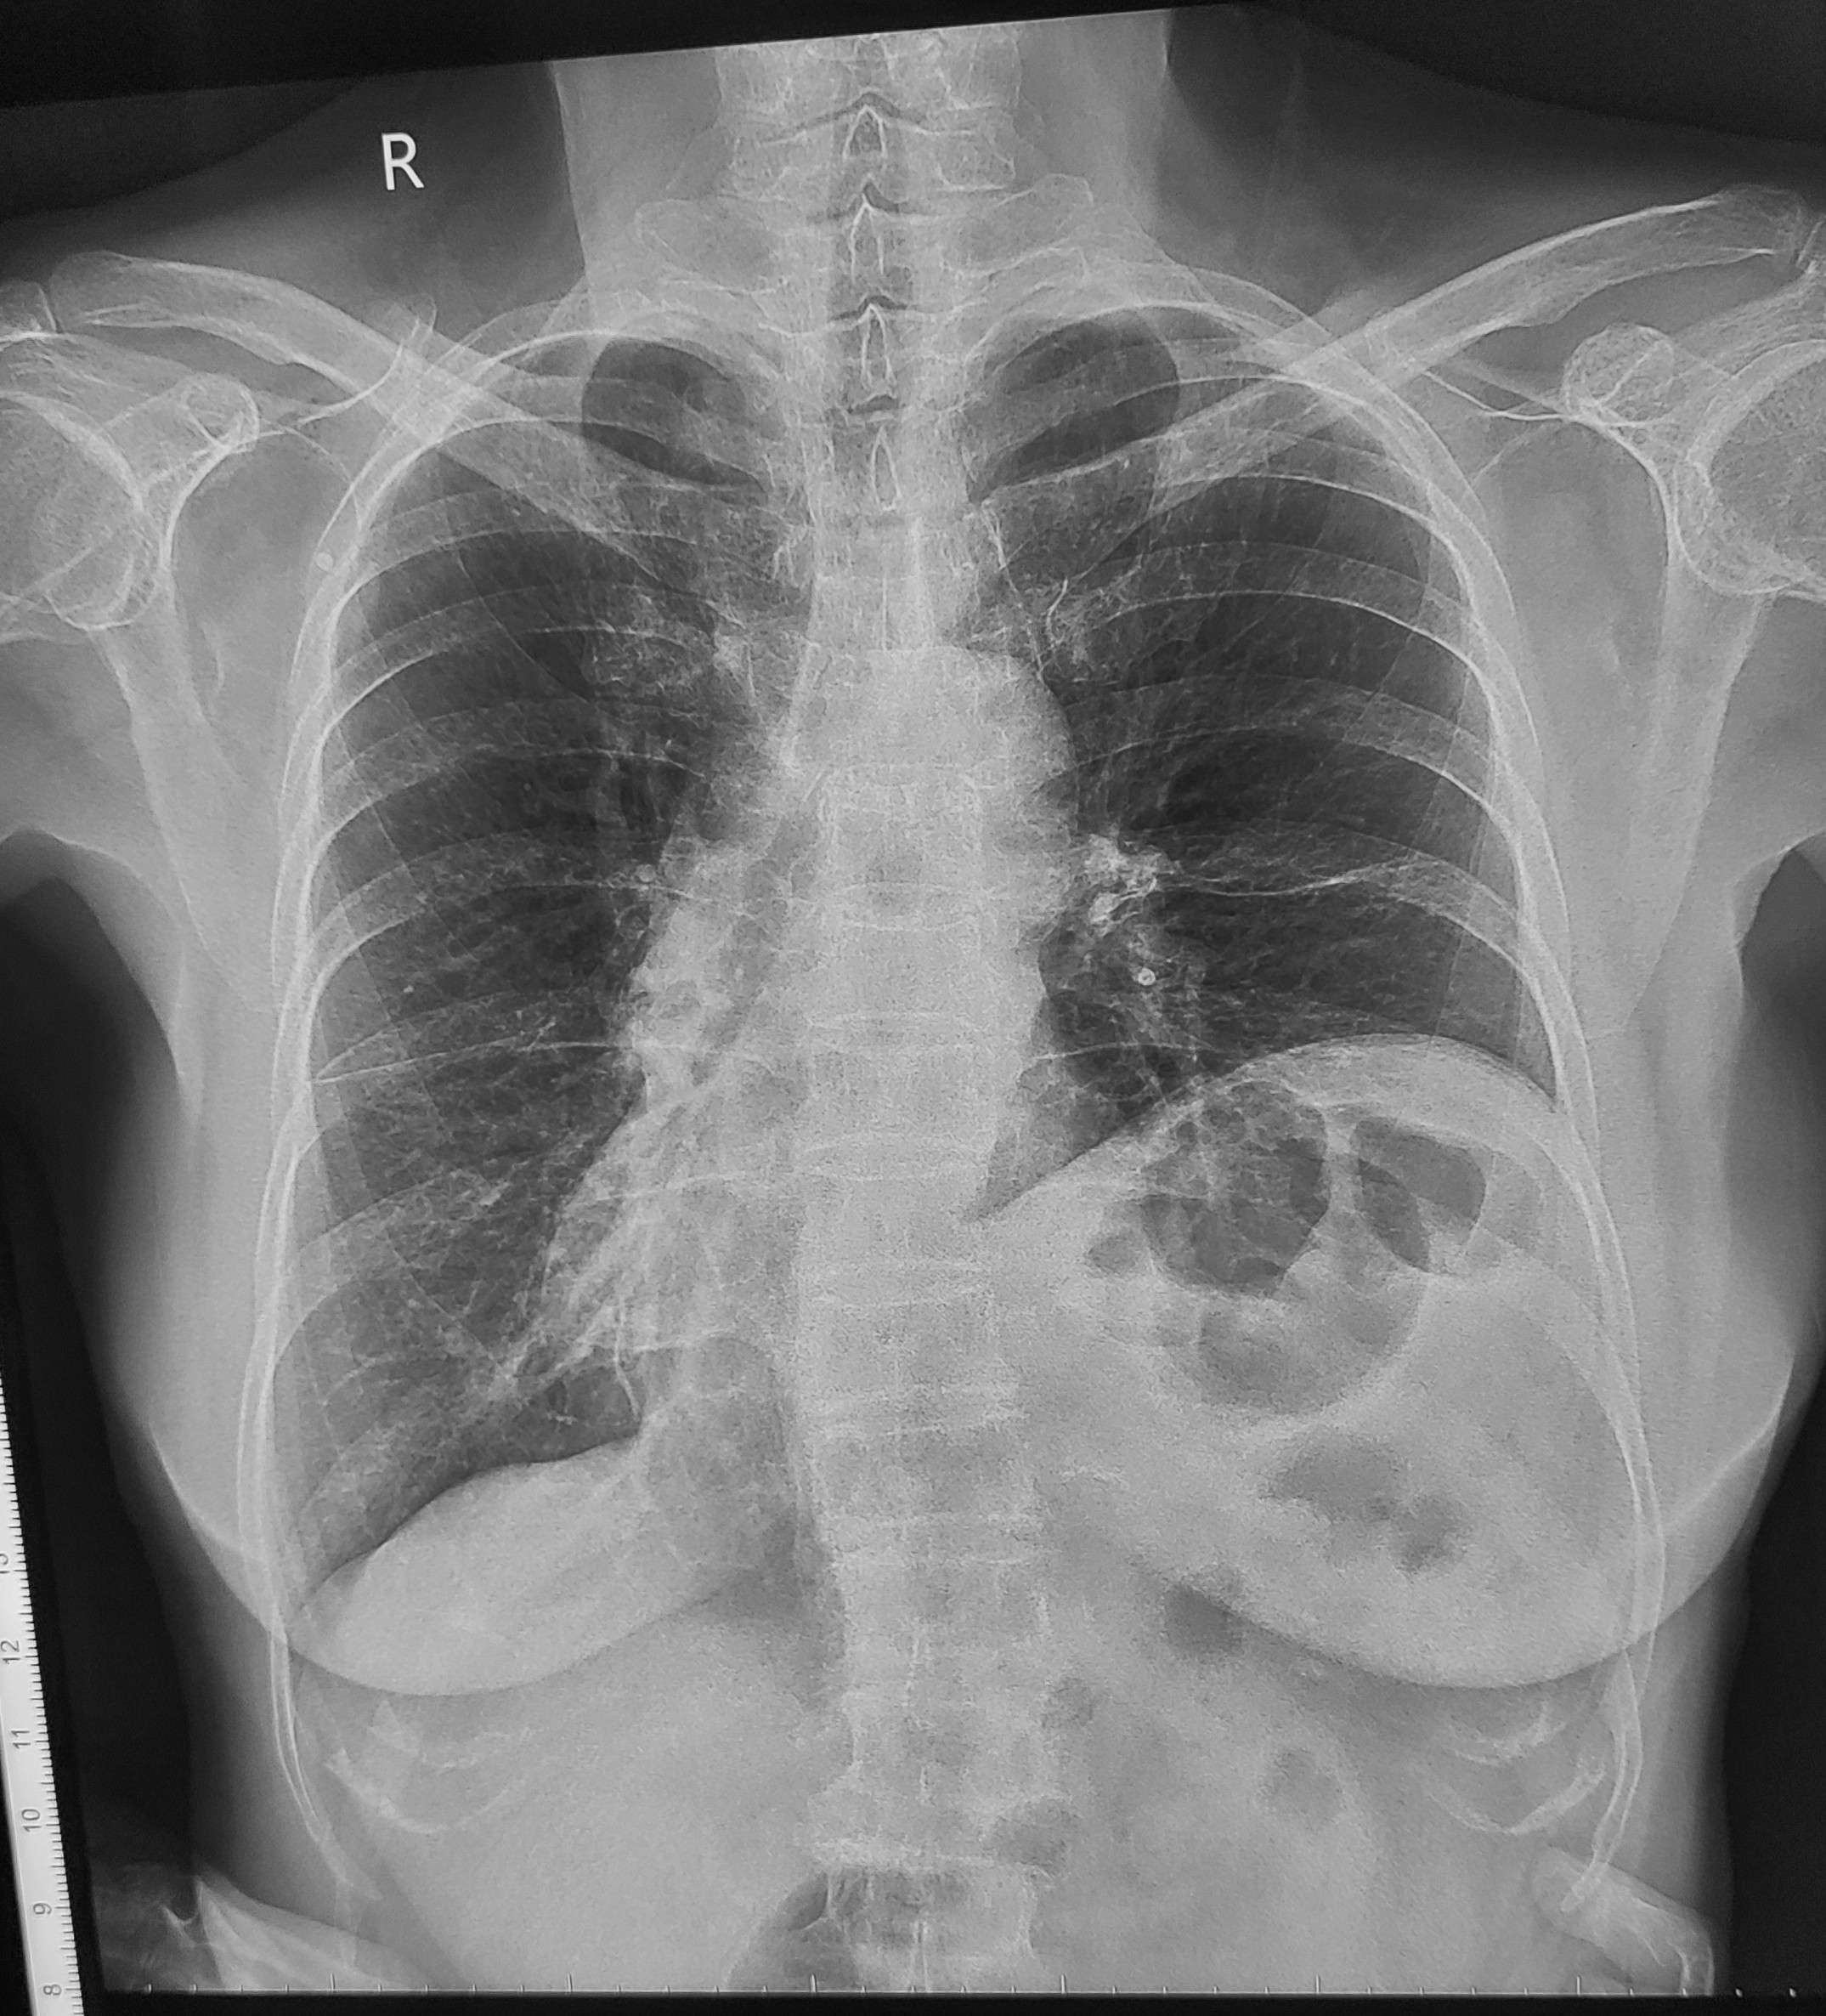

Bệnh nhân nữ 22 tuổi. Đau ngực khi thở trong vài ngày nay và khó thở. Đến phòng cấp cứu do các triệu chứng này, với CRP tăng nhẹ 44, D-dimer 5.2 µg/mL (bình thường <0.5 µg/mL), TnT bình thường, CTM bình thường. Không ghi nhận triệu chứng khác. Thỉnh thoảng hút thuốc, uống bia chủ yếu với bạn bè vào cuối tuần, không quá nhiều. Không có tiền sử bệnh mãn tính. Đang dùng thuốc tránh thai. HA 110/80, M 100.